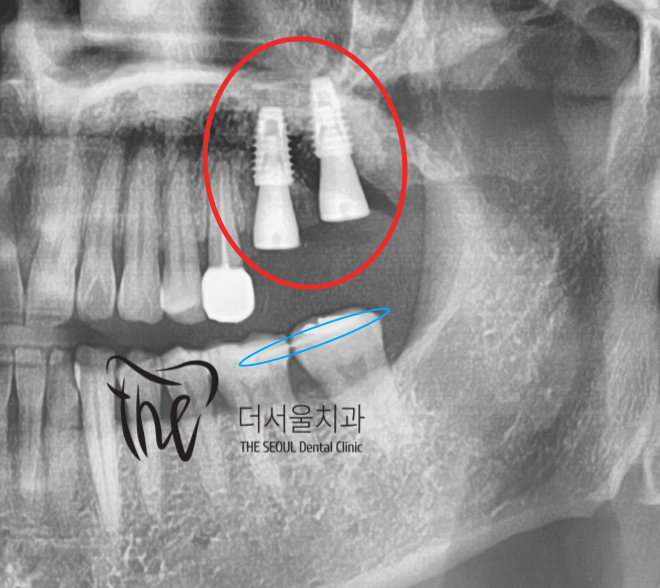

여하튼, 금니 통증 위치에

2개의 임플란트를 계획했고 예상 된 위치에

그대로 수술을 해드렸습니다.

나란히 픽스쳐 2개가 심겨진 것을 볼 수 있으며,

과거 apical lesion 의 범위가 컸기 때문에

천천히 지르코니아 크라운을 올려드릴 예정입니다.

다행히, 상악동거상술은 하지 않았기 때문에

회복기간은 다소 짧을 것으로 예상됩니다만

Sagittal plane, Coronal plane 에서 살펴보면

상악동과 임플란트 끝 쪽이 정말 가까이

붙어있는 것을 볼 수 있습니다.

앞서, 네비게이션 임플란트 진단 화면을

보여드렸는데 그대로 심겨진 것을 볼 수 있죠?

그만큼, 정확하다는 것을 뜻합니다.